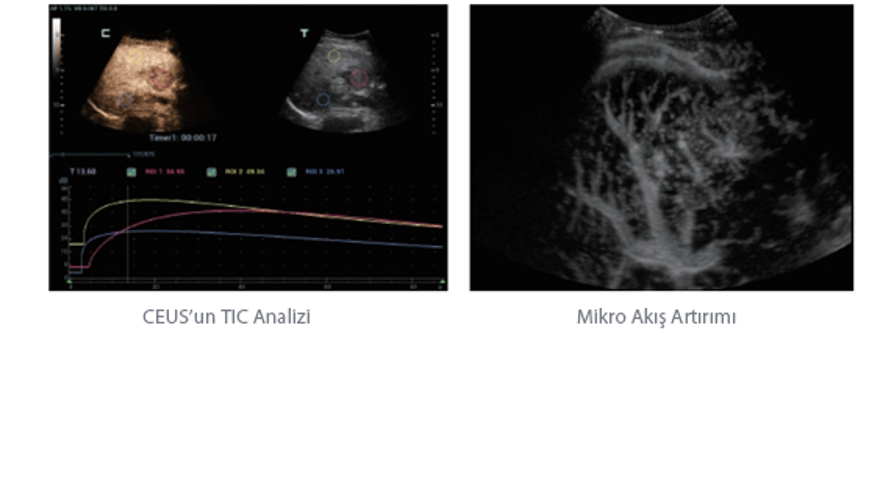

Mindray, ?irketin kuruldu?u gĂŒnden bu yana sĂŒrekli olarak tan?sal do?rulu?u iyile?tirmeye ?al??maktad?r. Devrim niteli?indeki ZONE Sonography? Teknolojisi ile desteklenen Resona 7ânin yeni ZST+ platformu, b?lge g?rĂŒntĂŒsĂŒ alma ve kanal veri i?leme ?zellikleri ile ultrason g?rĂŒntĂŒsĂŒ kalitesini daha ĂŒst bir dĂŒzeye ??kar?yor.

Resona 7, ĂŒstĂŒn dĂŒzeyde g?rĂŒntĂŒ kalitesine ek olarak, vaskĂŒler hemodinamik de?erlendirmesi i?in devrim niteli?indeki V Ak??? ile fetĂŒs CNS tan?lamas? i?in 3 boyutlu veri kĂŒmesinden dĂŒzlem g?rĂŒntĂŒsĂŒ alma konusunda en iyi birime sahip oldu?undan, klinik ara?t?rma yeterliklerini de art?rmaktad?r. En sezgisel, harekete dayal? ?oklu dokunmatik i?letim ile tĂŒm temel klinik ?zellikleri bir araya getiren Resona 7, ultrason yenili?i konusunda ger?ek anlamda yeni dalgalara ?ncĂŒlĂŒk ediyor.